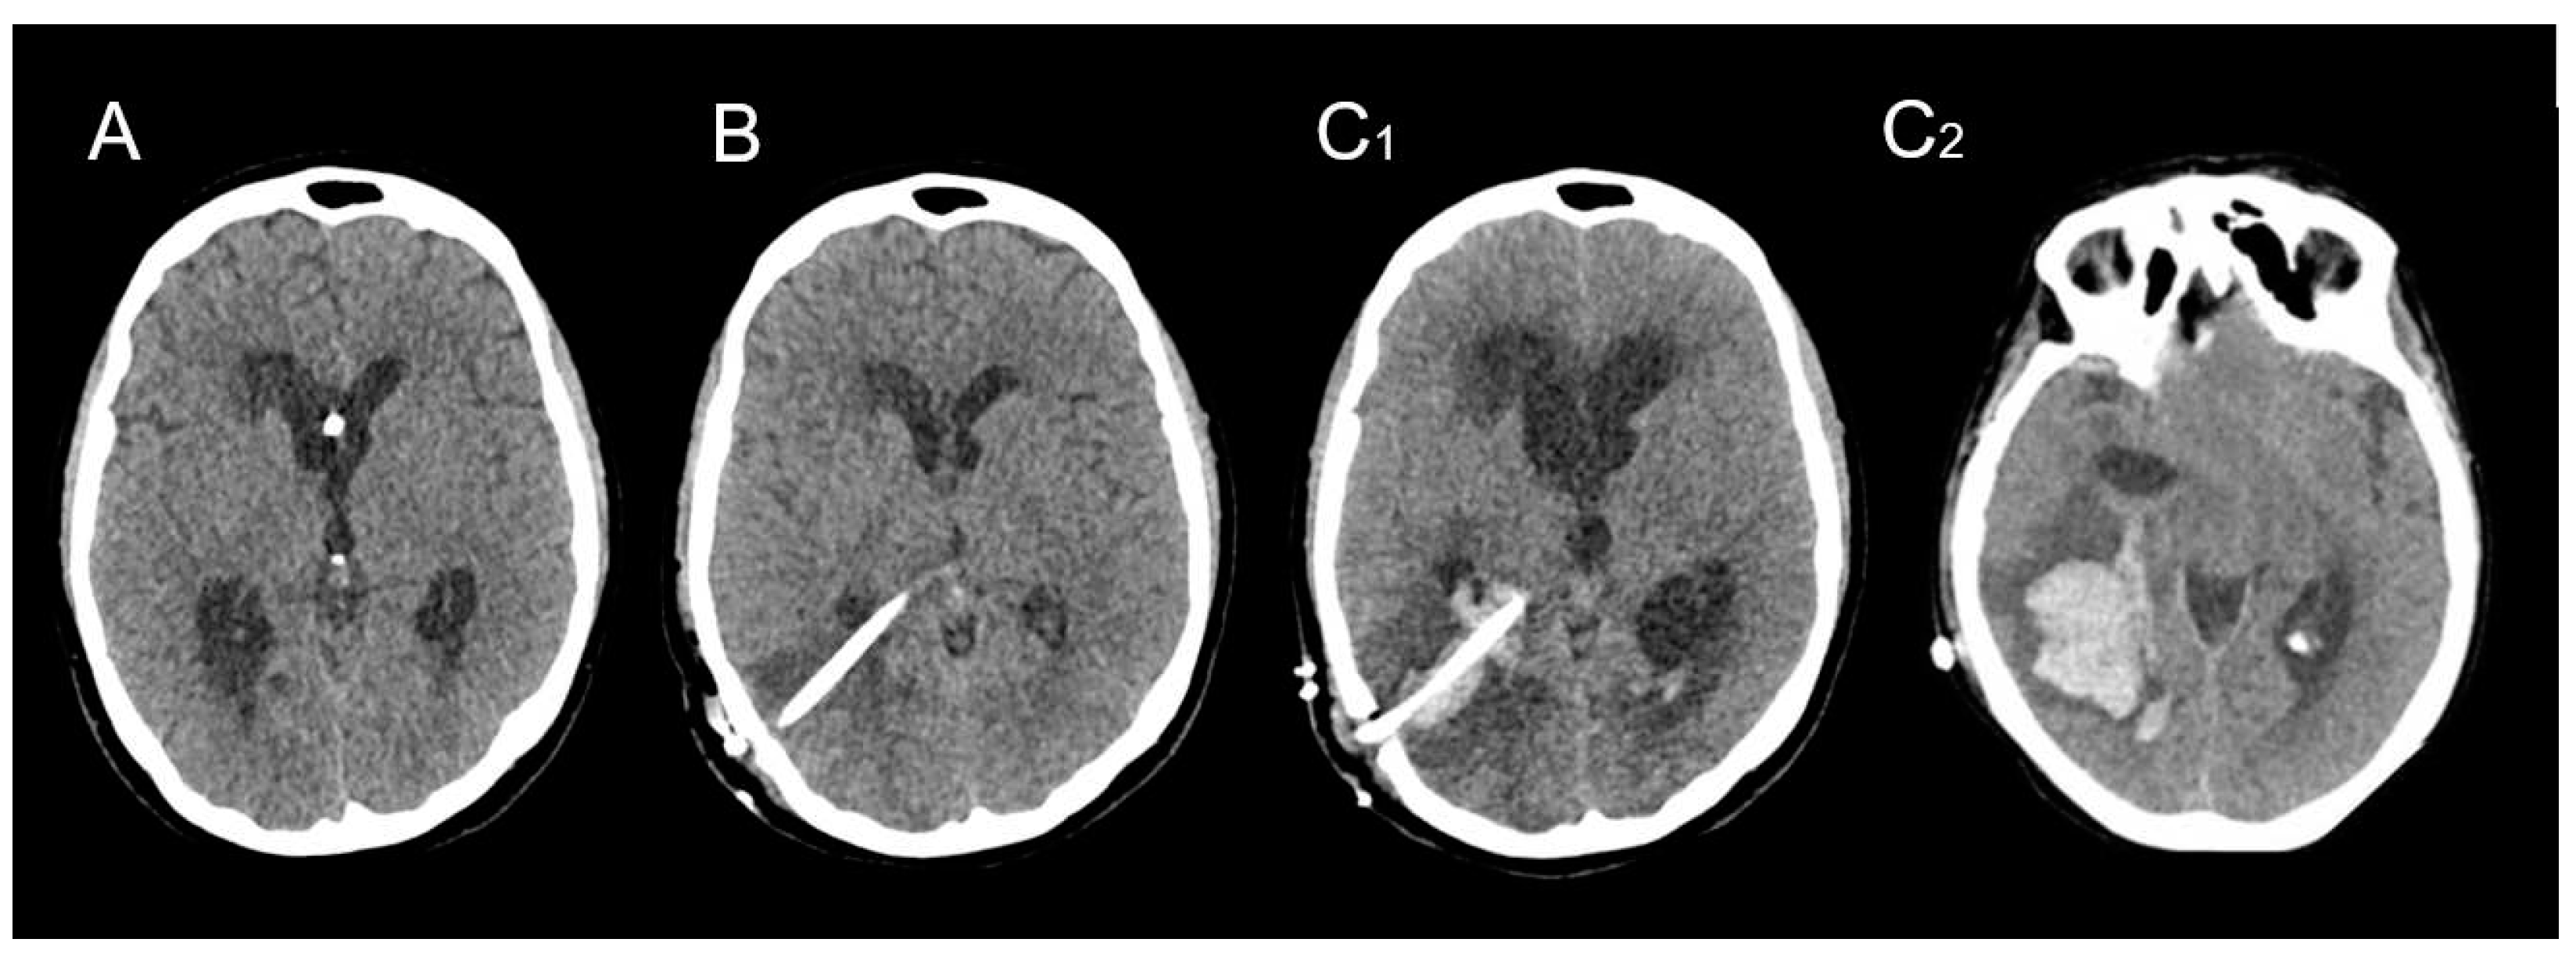

- The location of the hematoma was consistently distant from the arteriovenous malformation (AVM) nidus, surrounding the trajectory of the ventricular catheter.

- The occurrence of the hemorrhagic complication transpired several weeks after the initial AVM rupture and several days after the placement of the VPS.

- Catheter-related DICH manifested in all 10 cases without any evident coagulation disorders or other identifiable risk factors.